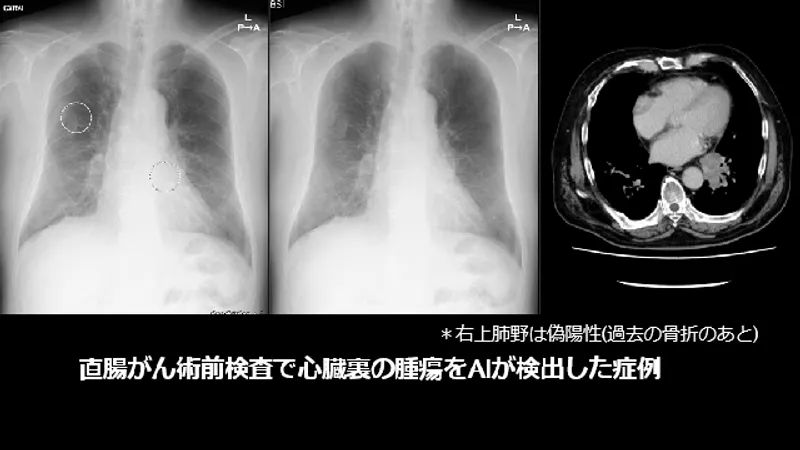

以前から提供している胸部読影支援の画像処理「Bone Suppression処理(胸部骨減弱処理)」や「Temporal Subtraction処理(胸部経時差分処理)」と併用することも可能です。 Bone Suppression処理で骨を減弱させることで、骨と重なった病変の視認性が向上し、AIと併用することによって、より読影精度の向上が期待できます。 また、Temporal Subtraction処理で現在と過去の差分画像を生成すると、経時的な変化が可視化されるので、経過観察が容易になります。

慶應義塾大学病院にて実施したCXR Finding-i読影実験の結果 AI無し読影にて見逃された病変の内、 経験の浅い医師で 67% (55/82病変)、 経験の豊富な医師で 66% (23/35病変) がAI使用により拾い上げられました。